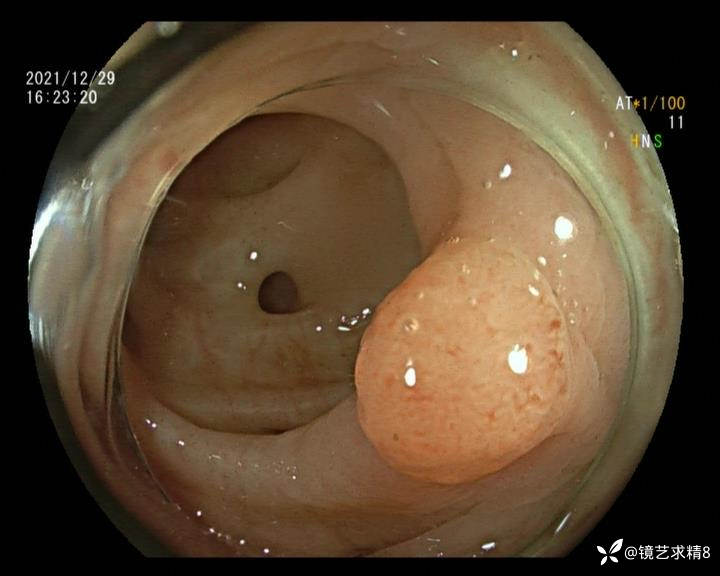

患者以消化道出血入院,胃镜未见异常,肠镜进入乙状结肠就看到很多憩室,同时还看到肠腔用清肠药后移动下来1枚尖锐的枣核,这么多憩室,这个枣核扎入憩室的机会非常大,推测应该是掉入一坑🕳就算出来还会有很多坑🕳🕳🕳等着,掉入憩室内很容易刺破血管,这可能就是消化道出血的原因,继续前进可以看到有一些憩室内翻,还有一些息肉,问题来了,那么多憩室,犯罪分子是抓住了,它在那些憩室内作过案?到达回盲部后挨个冲洗,但憩室大小又不足以把镜头进入憩室内观察,针对有血块的憩室冲洗后可疑出血的以夹子闭合或套扎,取出枣核,如果有锥形透明帽可能钻入憩室精准电凝效果更好,若内镜下操作失败介入治疗成功率更高,经内镜下治疗后观察未再出血出院。